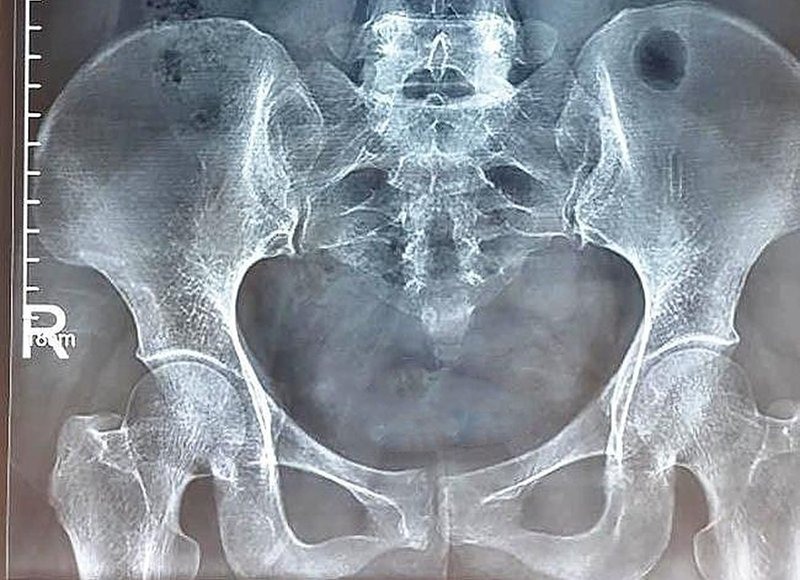

Chụp X quang hệ tiết niệu là một phương pháp sử dụng hình ảnh để chẩn đoán, đánh giá các cơ quan và cấu trúc trong hệ tiết niệu của cơ thể bao gồm thận, bàng quang và ống niệu.

Phương pháp này sử dụng tia X để tạo ra hình ảnh hai chiều của các cơ quan, cho phép bác sĩ đánh giá kích thước, hình dạng, vị trí và chức năng của chúng.